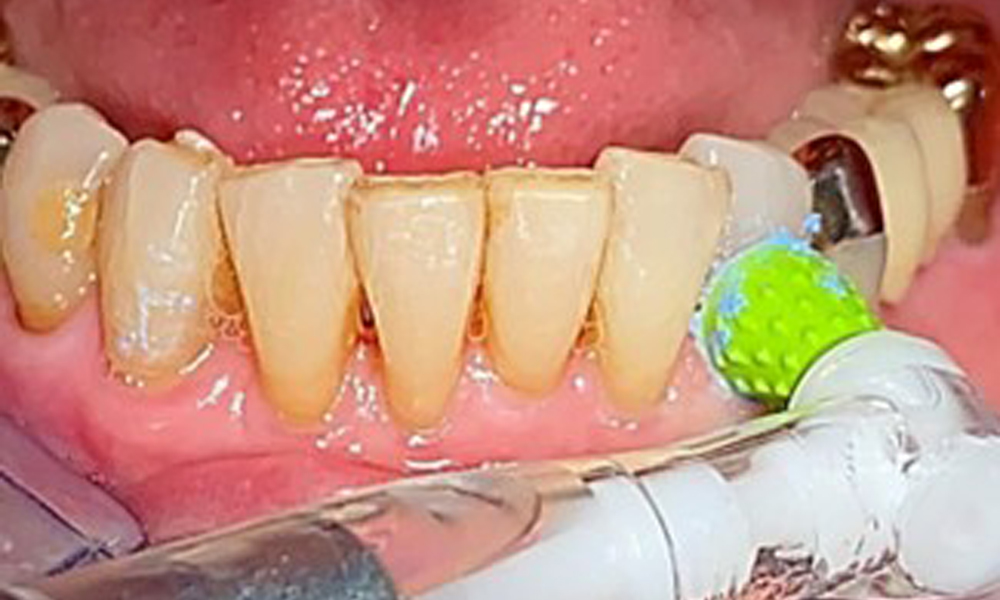

Selective polishing of tooth 33 (Proxeo Twist, W&H, shown here)

Fig. 13: Selective polishing of tooth 33 (Proxeo Twist, W&H, shown here)